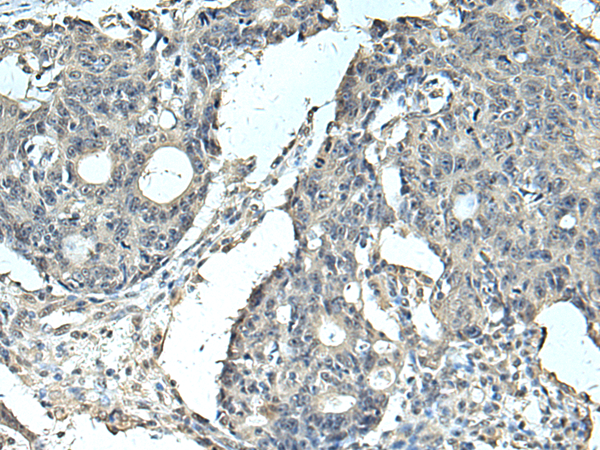

分类: 科研抗体货号: P10391别名: GMPR1; GMPR 1应用: IHC反应种属: Human, Mouse, Rat